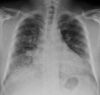

Cuando una masa o nódulo pulmonar es muy periférico, hay que diferenciarlo de una lesión extrapulmonar…

Nos fijaremos en el ángulo que forma la lesión con la pared torácica:

• Obtuso. Orienta hacia masa extrapulmonar.

• Agudo. Probablemente esté dentro del parénquima pulmonar.

Arriba: masa extrapulmonar (ángulo obtuso con la pared torácica). Abajo: masa intraparenquimatosa (ángulo agudo).